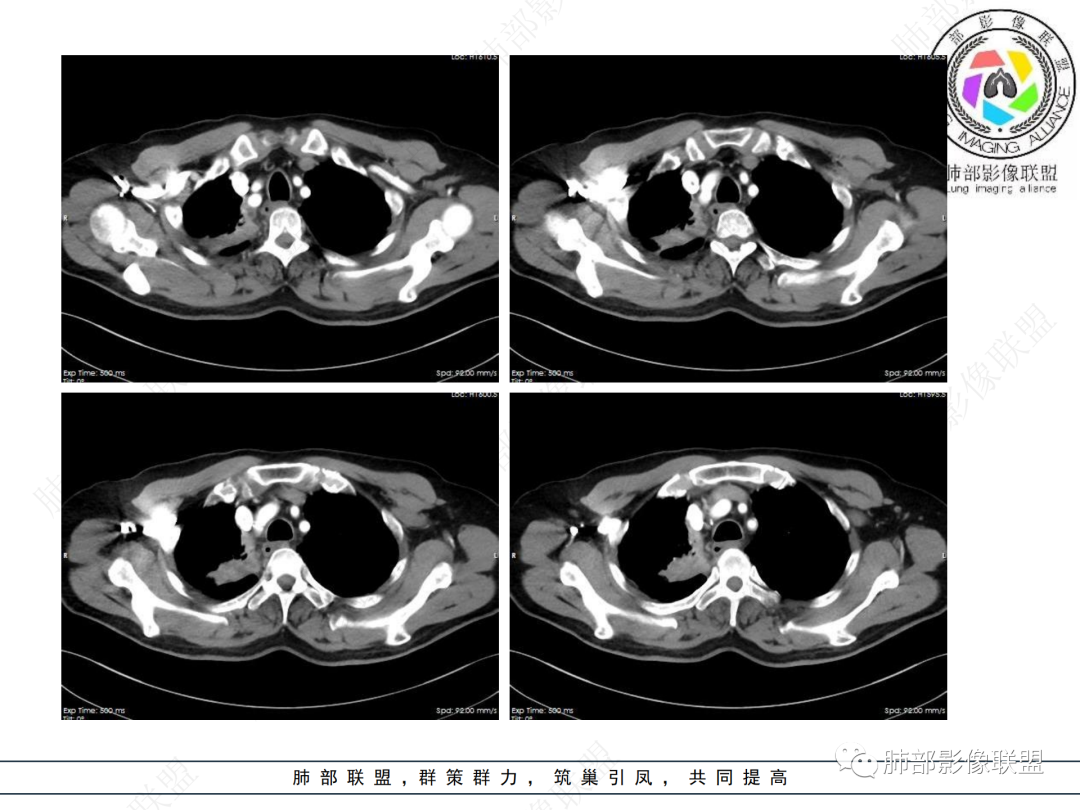

右肺上叶尖后段不规则斑块病灶,后缘以斜裂为界,有边缘平直,周围见纤维及多发小卫星灶,邻近胸膜反应性增厚,纵隔胸膜下少量积液,同时右肺中叶内侧段支气管扭曲及牵引性扩张,周边见爬行征,胸廊入口变窄,纵隔未见淋巴结肿大,综合上述慢性炎性肉芽肿,结核可能性大,支气管镜肺泡灌洗!

右上胸廓较对侧慢性缩小

结合本病例,老年男性患者,慢性病程,急性加重,无吸烟史,影像学表现为右肺上叶尖后段斑片实变密度影,整体边界清晰,边缘平直收缩为主,周边散在纤维条索影,内部见支气管内粘液栓,血管影走形正常,没有明显破坏,增强扫描明显强化,缺乏典型分叶毛刺、胸膜改变,病灶也未显示清楚的磨玻璃勾边,病灶大而肺门纵隔未见肿大淋巴结,综合考虑慢性炎性肉芽肿可能性大。但恶性,结核能完全排除吗?我想对临床医生来说还是有很大考验的。